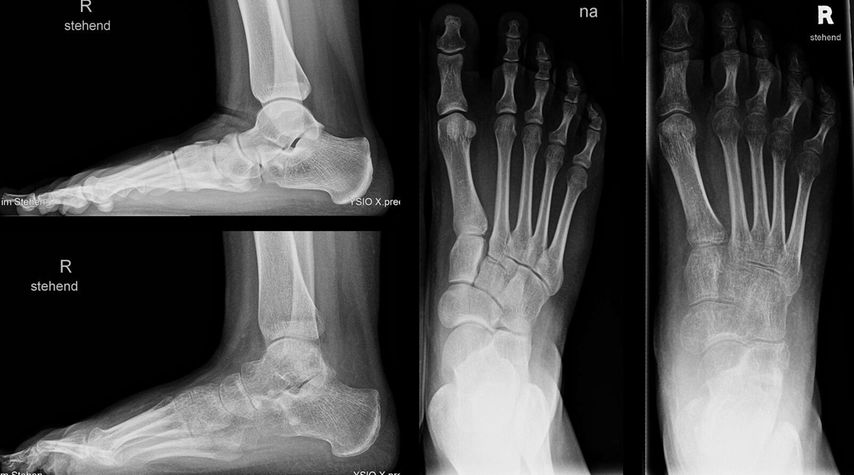

Bei einem 9-jährigen Mädchen mit angeborenem Knick-Senk-Fuß beidseits wurde ein kommerziell verfügbarer Allograft-Knochenblock zur Evans-Osteotomie erfolgreich angewendet. Im Rahmen einer ersten Operation wurde der rechte Fuß adressiert (Abb. 1) und im Verlauf ein Jahr später das gleiche Verfahren auf der Gegenseite problemlos eingesetzt. In der Verlaufskontrolle 1 Jahr postoperativ zeigen sich eine gute knöcherne Einheilung, eine adäquate Fußaufrichtung und eine Verlängerung der lateralen Säule. Das Allograft ist nativradiologisch noch abgrenzbar. Ein weiterer Fall einer komplikationslosen Evans-Osteotomie mit kommerziellem Allograft-Knochenblock ist der eines 14-jährigen Jungen mit Knick-Senk-Fuß links. Abgebildet ist die Verlaufskontrolle 6 Wochen postoperativ, wobei im Rahmen der ambulanten Kontrolle die Kirschnerdrähte nach 6 Wochen entfernt wurden. Ein Folgeröntgen ist noch ausständig (Abb. 2). Bei einer 15-jährigen Patientin mit schmerzhaftem Knick-Senk-Fuß beidseits zeigt sich ebenso eine adäquate Fußkorrektur in der Jahreskontrolle nach Evans-Osteotomie mit Allograft-Knochenblock rechts. Eine Versorgung der Gegenseite ist geplant (Abb. 3). Auch im Fall eines 11-Jährigen mit Serpentinenfüßen kamen bereits Allograft-Knochenblöcke erfolgreich zum Einsatz: Präoperativ zeigte sich hier ein Rückfußvalgus mit Vorfuß adductus und damit verkürzter lateraler Fußsäule. Als operative Sanierung wurde eine Fußkorrektur durchgeführt, die Aspekte einer modifizierten Cotton-, Evans- und Cuboid-Osteotomie enthält. In der postoperativen Röntgenaufnahme 8 Wochen später zeigte sich eine gute knöcherne Einheilung bei stabiler Korrektur, sodass die Drähte gezogen werden konnten (Abb. 4).

Abb. 1: 9-jähriges Mädchen mit Knick-Senk-Fuß, prä- und postoperative Röntgenaufnahmen des rechten Fußes, vor und nach Evans-Osteotomie. Postoperativ zeigt sich eine adäquate Fußaufrichtung und Verlängerung der lateralen Säule